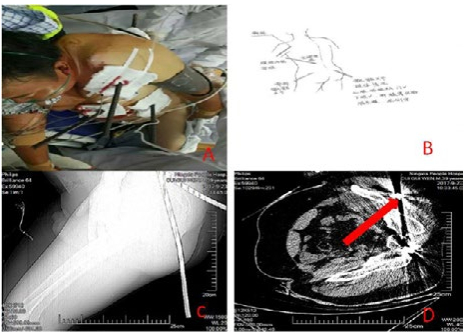

患者男,39岁,于2017年9月23日在建筑工地作业时不慎从7 m高处坠落,致全身被多根钢筋贯通伤,伤后即感全身疼痛,呼吸困难,神志清楚,经消防人员初步处理后由我院院前人员给予初级创伤救治,通知院内启动应急预案系统。入院后查体血压88/60 mmHg(1 mmHg=0.133 kPa),脉搏110次/min,R 20次/min,血氧饱和度95%,神清,面色及睑结膜苍白,强迫左侧卧位,可见1根钢筋(长约50 cm)自左肩胛区左前胸部,三根钢筋分别自左臀部至左肩部贯通,右臀部至上腹部贯通,左腰部贯通左上腹(图 1),伤口出血不止,呼吸活动左右不一致,左肺呼吸音减弱,右肺呼吸音清晰,四肢活动尚可,腹部压痛及反跳痛查体不配合。实验室检查WBC 12.66 ×109/L;其余化验结果均正常。腹部B超示:①右肝、胰腺显示不清;②脾周少量积液,深约1.2 cm,因伤者身上横着钢筋,无法以正常体位CT扫描,初步诊断为“胸腹部钢筋贯通伤;创伤性休克”。患者影像学资料见图 1

A:患者入院情况;B:手绘图;C、D:影像学检查结果 图 1 患者资料